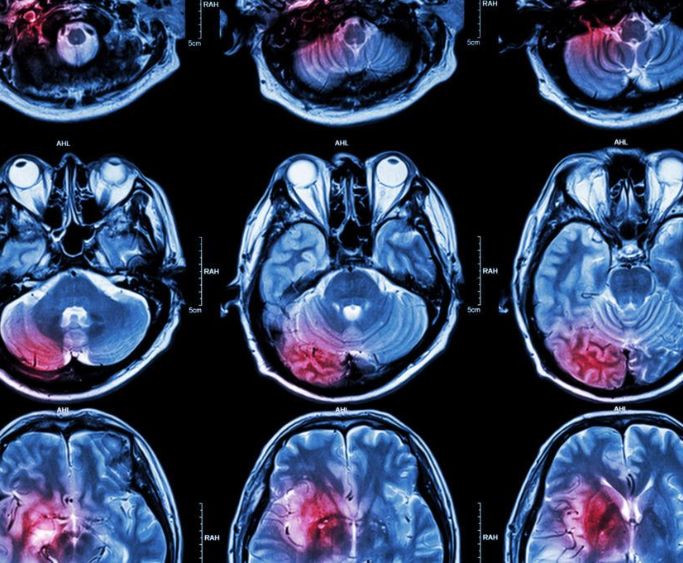

However, a turning point came when he collapsed while traveling, prompting an urgent medical examination that revealed a brain tumor in his frontal lobe.

This area of the brain, responsible for managing emotions, personality, and judgment, shed light on his erratic behavior. The diagnosis was a double-edged sword, bringing both clarity and a daunting path to recovery.